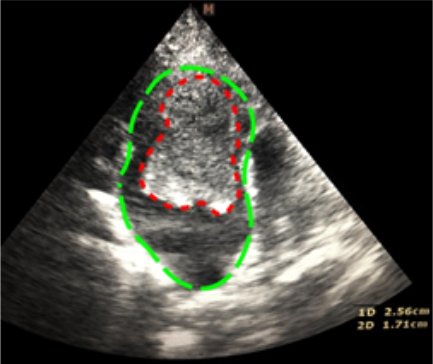

Эхокардиография (рис. 3–5). Данный метод позволяет выявить основное заболевание сердца. Также можно выявить изменение кровотока и замедленное прохождение крови в ушке или в полости левого предсердия посредством импульсно-волнового доплера. У некоторых кошек тромб, формирующийся (в виде облака) или зрелый, можно увидеть в левом предсердии.